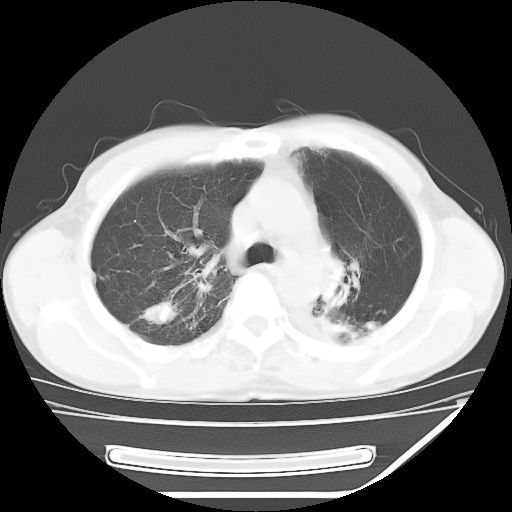

男,59岁,“结核性胸膜炎”30余年,胸部经常疼痛,多次x检查提示“肺部”炎症。腹部疼痛5日,b超提示:“肝内短管结石,余显示不清,建议进一步检查。”

两肺结核并右侧胸腔积液;脾脏、腹腔及腹膜后淋巴结结核[陈旧性];肝内胆管结石

胸部腹部都是结核(双肺。纵隔淋巴结,肝脏,脾脏,肠系膜)

两肺结核并右侧胸腔积液;脾脏、腹腔及腹膜后淋巴结结核[陈旧性];肝内胆管结石。直肠息肉?